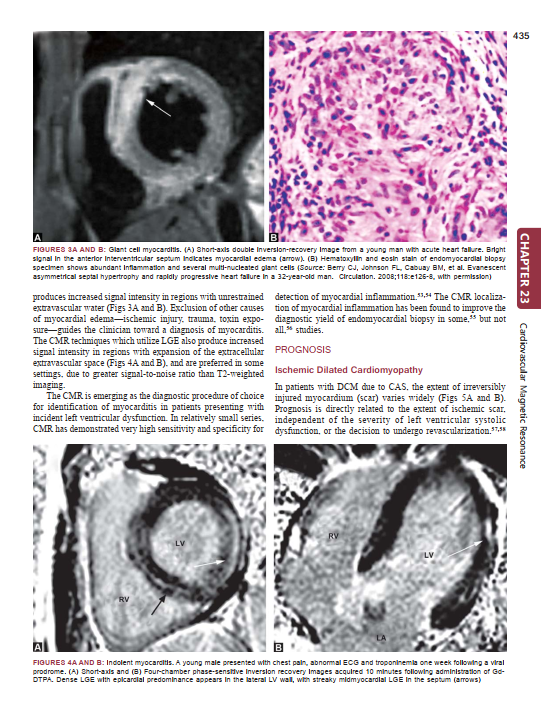

Description